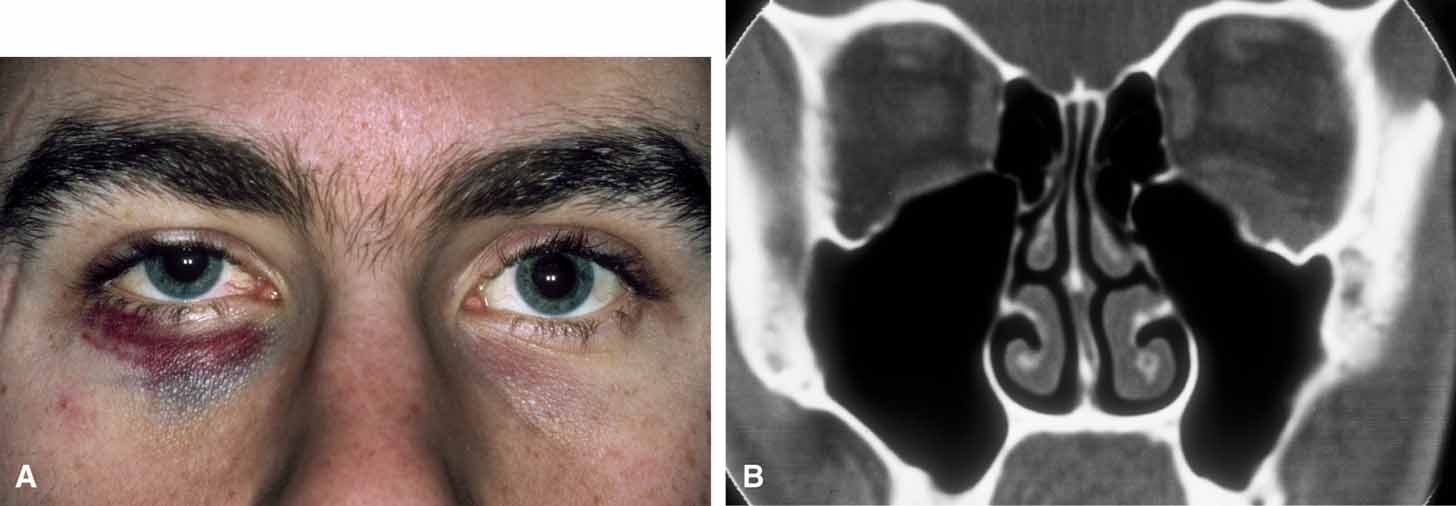

Hematic cysts are uncommon, and the clinical history and ophthalmic findings rarely are diagnostic.48–50 Mass effect with proptosis, globe displacement, and motility disturbance are common with chronic hematic cysts. Spontaneous eyelid ecchymosis and edema may suggest this diagnosis (Fig. 10). In acute hematic cysts, optic nerve signs may be present, including decreased vision, afferent pupillary defect, and choroidal folds.51

Fig. 10 A. Spontaneous periorbital ecchymosis and diplopia in a man who had undergone a left orbital blowout fracture 5 years previously suggest the presence of a hematic cyst. B. Computed tomogram shows the left globe and a previously placed Silastic plate displaced superiorly by the expanding hematic cyst in the floor of the left orbit.